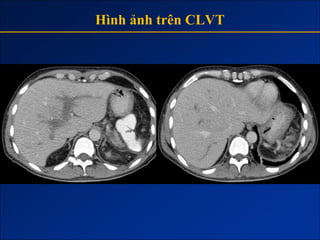

Hình ảnh trên CLVT

- Giai đoạn sớm:

+ Gan to.

+ Tăng tỷ trọng do xơ hóa.

- Giai đoạn muộn:

+ Gan biến đổi hình thái và đường bờ.

+ Dấu hiệu tăng ALTMC.

+ Dấu hiệu khác:

Dịch ascite – Lách to – Dày thành TM.

Nốt tân tạo.

Biến chứng (HCC).

1. Gan biến đổi hình thái và đường bờ